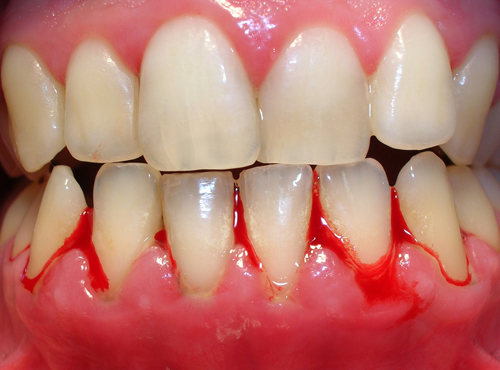

Chảy máu nướu

Chảy máu khi đánh răng là một dấu hiệu rõ rệt của viêm nướu. Nướu có thể chảy máu ngay cả khi bạn thực hiện các hành động đơn giản như đánh răng hoặc dùng chỉ nha khoa. Nếu bạn gặp phải tình trạng này, hãy đến gặp bác sĩ nha khoa càng sớm càng tốt.